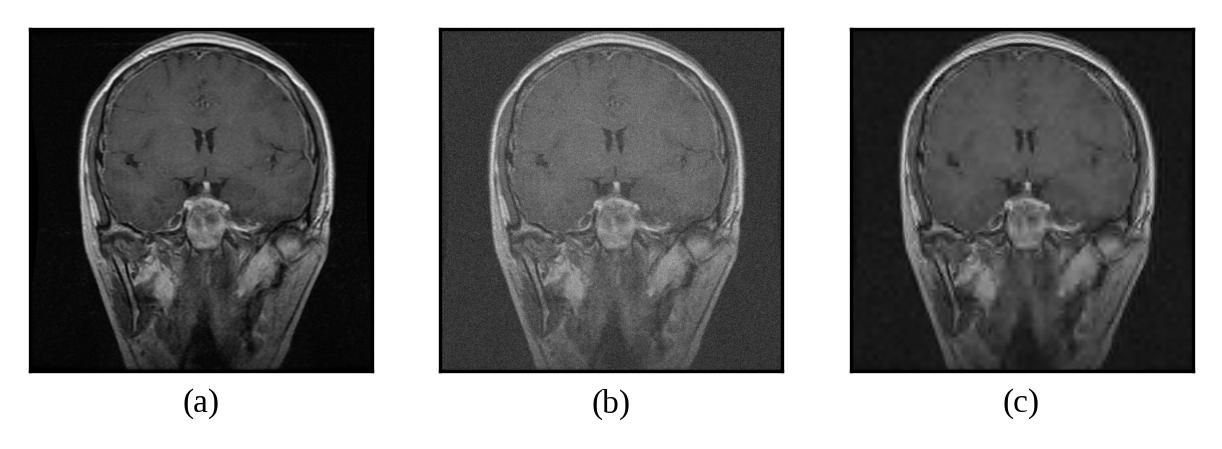

Representative denoising results are illustrated in Figures 2 through 7, demonstrating the visual improvement achieved by both thresholding methods across different noise levels.

Refer to caption

Figure 2: (a) Original Image, (b) Noisy Image(μ=0\mu=0, σ=10\sigma=10), (c) Denoised Image (with threshold value τbayes\tau_{bayes})